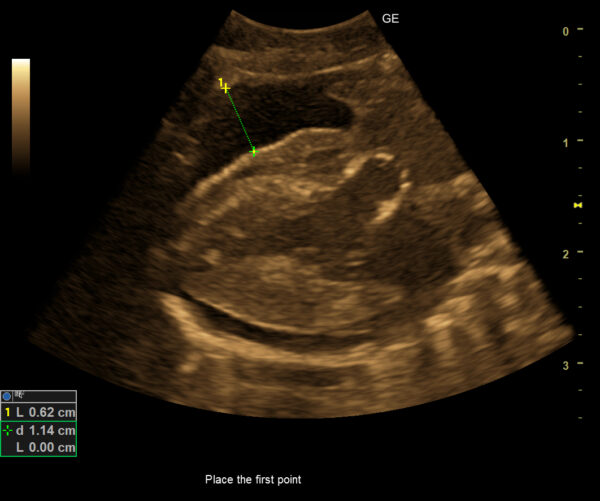

Foto. archiwum prywatne. Płyn w worku osierdziowym u świnki morskiej